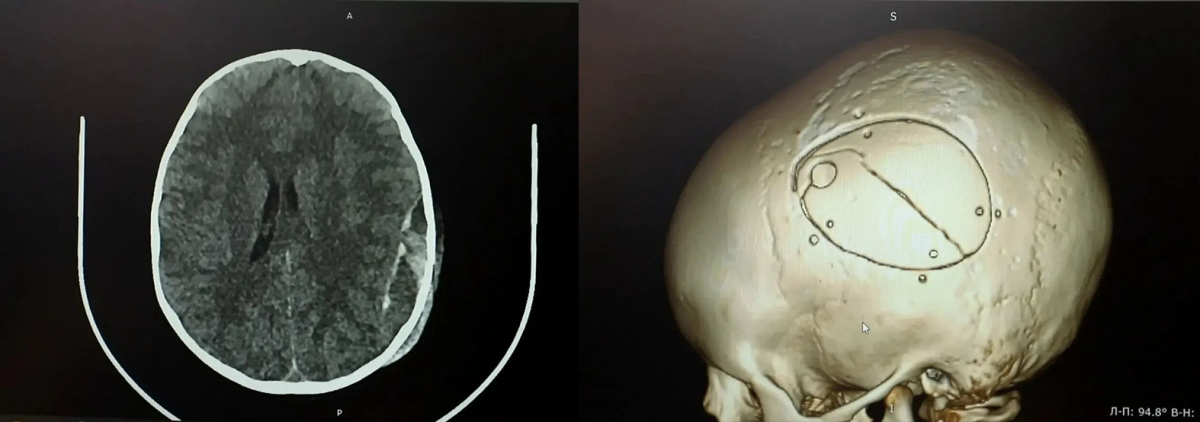

Как сообщает Минздрав Кузбасса, сразу после происшествия у ребёнка не было видимых травм головы, однако на следующий день он начал отказываться от еды. Родители обратились в больницу, где обследование выявило серьёзные повреждения – перелом черепа и острую эпидуральную гематому.

Мальчика экстренно доставили в операционную. Нейрохирурги провели сложную операцию – костно-пластическую трепанацию черепа, удалили гематому и остановили кровотечение.